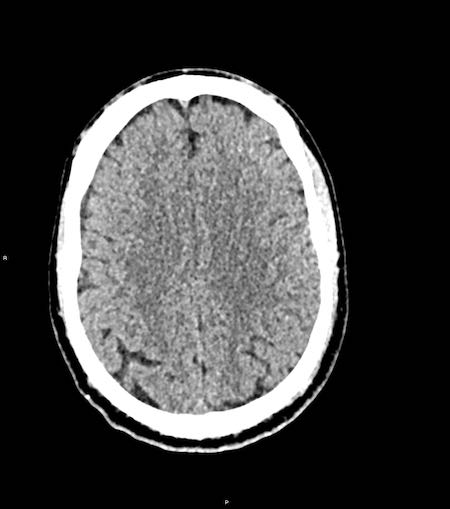

Tụ máu dưới màng cứng đồng tỷ trọng

Khi tụ máu dưới màng cứng tiến triển theo thời gian, tỷ trọng của khối tụ máu sẽ giảm dần và có thể tương đương với tỷ trọng của nhu mô não, khiến việc phát hiện tổn thương trở nên khó khăn.

Đây là trường hợp tụ máu dưới màng cứng đồng tỷ trọng rất khó phát hiện (các mũi tên).

Lưu ý rằng ở mức cắt cao hơn có tụ máu dưới màng cứng hai bên.